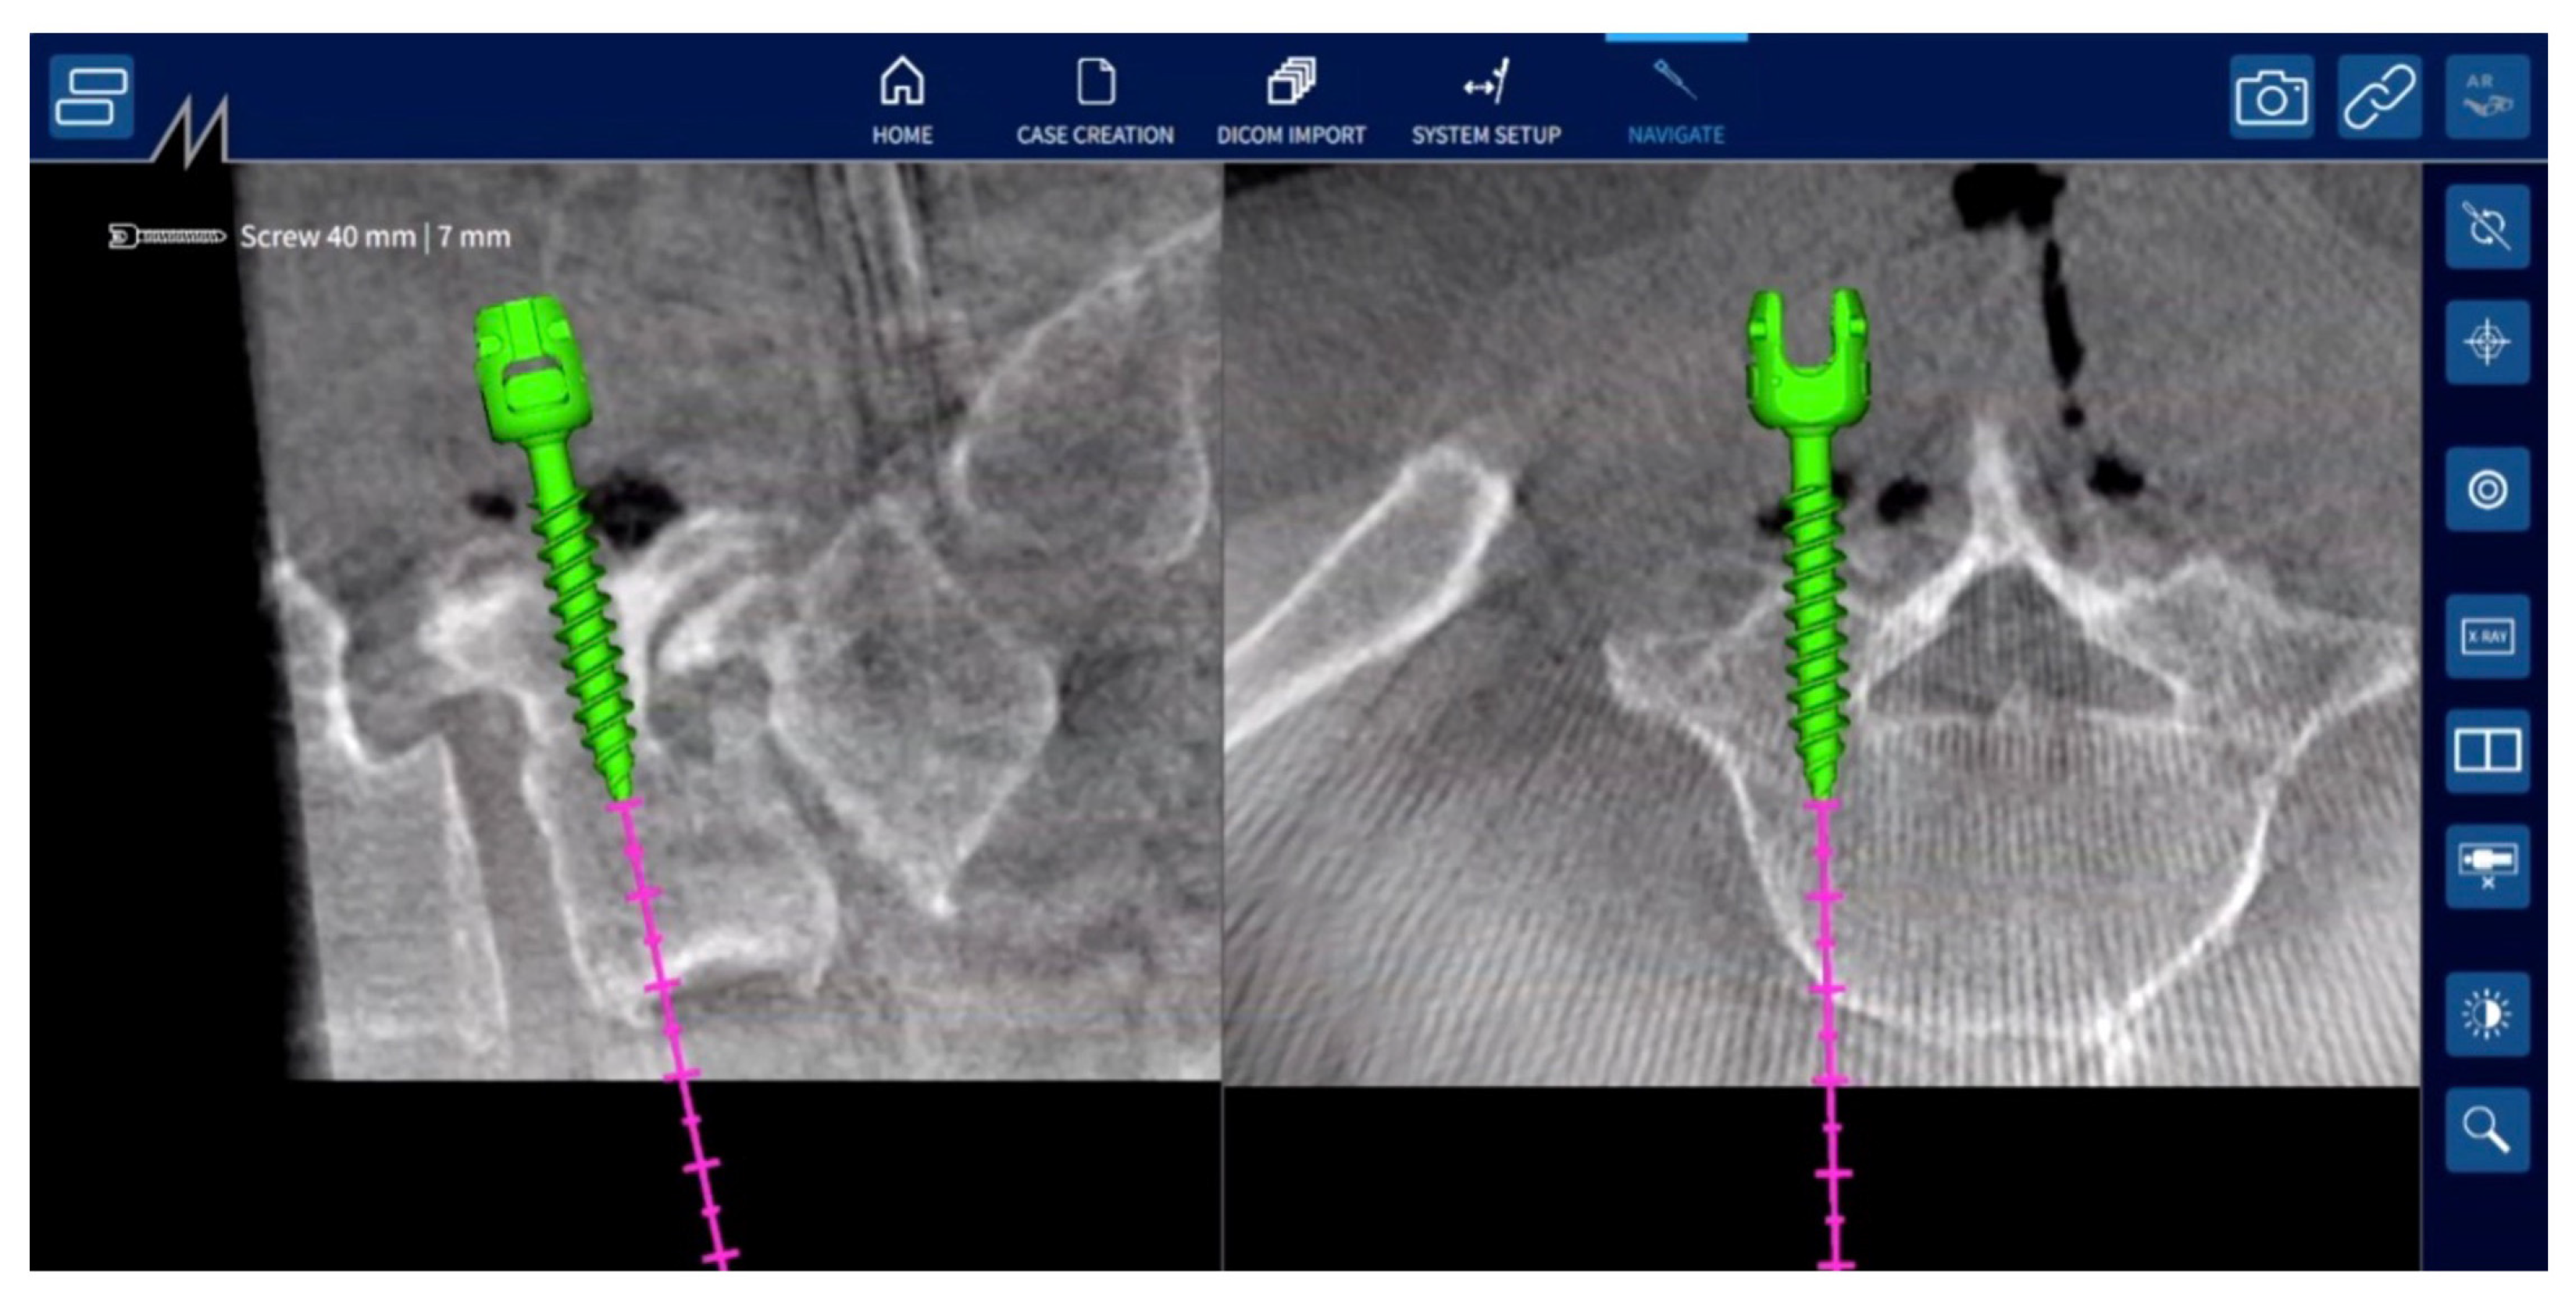

Then, the fiducial can be removed from the clamp and the target can be mounted onto it. Additionally, the small infrared camera is mounted on the surgical instruments, such as the pedicle probe, screw tap, and screwdriver. Prior to beginning navigation, each instrument must be placed over the identification cavity of the clamp to be identified by the control unit. The accuracy of navigation was verified by contacting the tip of the pedicle probe with the clamp, the spinous process, and other landmarks on the bone surface. Under navigation guidance, the proper screw entry point on the bone surface is confirmed using a pedicle probe, and a screw entry hole is made using a high-speed drill. Then, a screw hole is made using a pedicle probe and screw tap, and the pedicle screw is inserted under navigation guidance (Figure 3). During the screw insertion procedures, the trajectory of the instruments is displayed on the screen in the transverse and sagittal planes of the 3D CT image (Figure 4). Hence, there is no need to use fluoroscopic guidance for pedicle screw insertion. Following the insertion of pedicle screws, surgeons perform additional procedures such as posterior decompression of neural tissue and interbody fusion to complete the surgery.

Figure 4.

Three-dimensional CT image in NextAR navigation system. During screw insertion procedures, such as pedicle probing, tapping, and screwing, the instrument’s trajectory is displayed on the screen in transverse and sagittal planes of the 3D CT image.